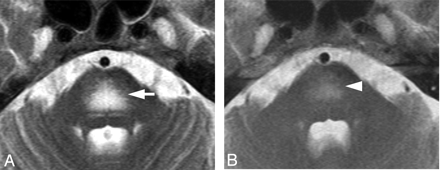

Case 8. Hyperintense lesion in the pons on a T2-weighted image in a 63-year-old woman. A, Axial T2WI shows symmetric hyperintense lesions in the center of the pons sparing the pontine tegmentum and ventrolateral pons (white arrow). DWI showed T2 shinethrough without diffusion restriction (not shown). B, T2WI after chemotherapy shows a decreased abnormal signal intensity in the pons on day 85 (white arrowhead).

Meningeal enhancement was observed in 2 patients (Fig 3A). In 1 of 2 patients with meningeal enhancement, the enhancement decreased just after treatment started. No surrounding edema or intraparenchymal enhanced lesions were observed. Postmortem examination revealed thickened vascular walls and necrotic and subendothelial tumor infiltration with abundant lymphocytes surrounding the vascular walls (Fig 3B). Masslike lesions were observed in 1 patient with multiple intraparenchymal focal enhanced lesions and mass effect (Fig 4A). No abnormal findings were found on DWI (Fig 4B). A gradual decrease in the contrast enhancement and mass effect of the lesions was observed after chemotherapy was started (Fig 4C). No postmortem examination was performed on this patient. The hyperintense lesions in the pons on T2WI without diffusion restriction or contrast enhancement were observed in 5 of 11 patients. This signal-intensity pattern was the only abnormal one in 4 of the 5 patients. All 5 patients showed symmetric hyperintense areas in the central pons, sparing the pontine tegmentum and ventrolateral pons (Fig 5A). The hyperintense areas in the pons decreased in size and intensity in all of the 4 patients treated (Fig 5B). In case 9, a follow-up MR imaging showed a decrease in the size of the lesion 3 days after treatment. Brain stem atrophy was not observed in any of these 4 cases after treatment.

Hyperintense lesions in the central pons on T2WI without enhancement or diffusion restriction were observed in 5 of 11 patients with IVL before treatment. This pattern in patients with IVL has not previously been reported in English-language literature, to our knowledge. The decrease of the lesions seen on MR imaging in 4 patients after treatment started strongly suggests that these lesions are a manifestation of IVL. The hyperintense lesions in the central pons, excluding the pontine tegmentum and ventrolateral region, on T2WI are similar to findings in pontine osmolytic demyelination syndrome and PRES in the brain stem or intracranial dural arteriovenous fistula with venous congestion.16–20 Five patients showing hyperintense lesions in the central pons on T2WI had no indication of osmolytic demyelination syndrome or typical PRES. Although there was no correlating pathologic evidence from the patients who presented with this pattern, 2 of the 5 postmortem examinations on other patients showed tumor cell infiltration into the vessels including the pons (Fig 6). We speculate that vascular occlusion in small veins and arteries by tumor cells results in venous congestion that could manifest as hyperintensity in the central pons on T2WI.